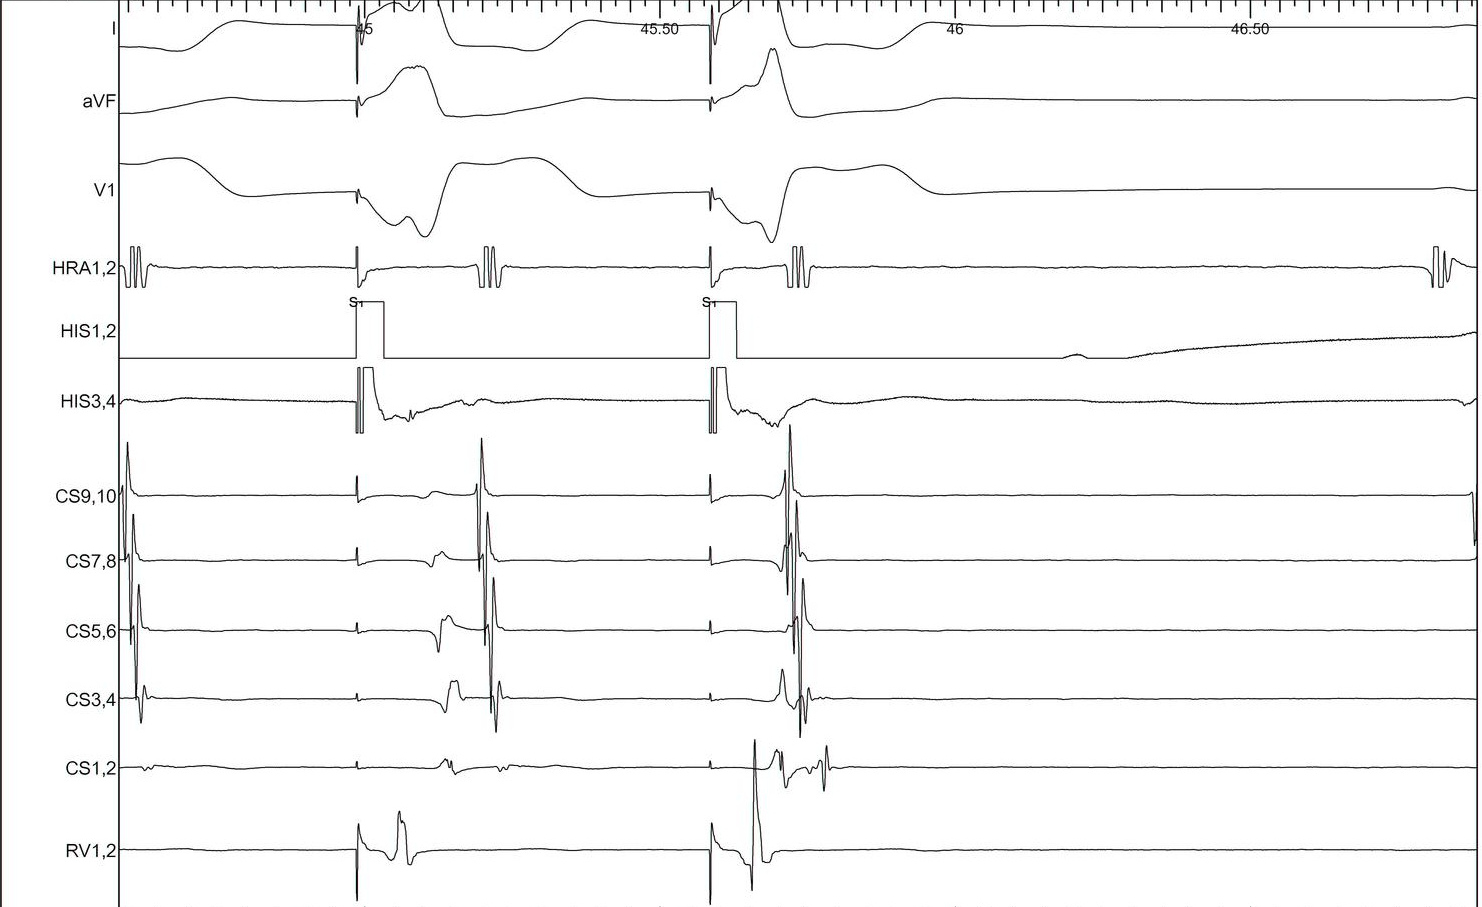

Tachycardia induction

• Chamber from which induced

• Induction dependent on critical AH prolongation

• Induction dependent on antegrade AP conduction block

Regular narrow QRS tachycardia

• A/V ratio

• Atrial activation

• VA time

• Ventricular overdrive pacing